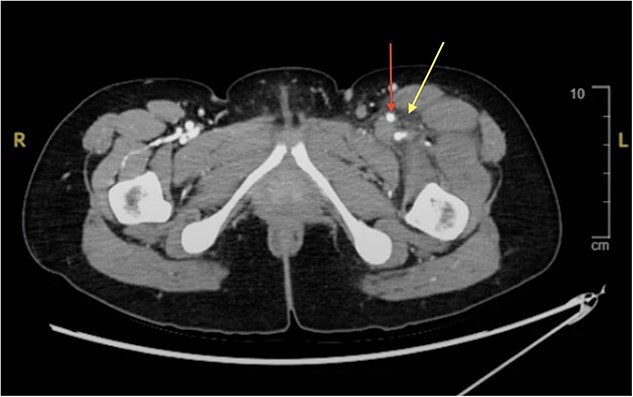

梅-瑟纳综合征(May-Thurner Syndrome, MTS)是由于左髂总静脉受压而导致深静脉血栓形成(DVT)。在深静脉血栓形成之前,MTS通常是无症状的。我们的病例是一名37岁的女性,她在最近的旅行和口服避孕药后出现左腿肿胀和疼痛。静脉双工超声证实深静脉血栓,CT血管造影排除肺栓塞。她接受了肝素抗凝治疗,并接受了机械取栓和支架置入术。她的症状在两天内得到改善,并在阿哌沙班和普拉维克斯的治疗下出院。该病例涉及一种独特的MTS患者表现,涉及一名患有不明原因左侧深静脉血栓的年轻女性,这种情况通常见于老年凝血障碍患者。

May-Thurner Syndrome (MTS) is caused by left common iliac vein compression, resulting in deep vein thrombosis (DVT). MTS is usually asymptomatic until DVT occurs. Our case features a 37-year-old woman who presented with swelling and pain in her left leg after recent travel and oral contraceptive use. Venous duplex ultrasound confirmed DVT and CT angiogram excluded pulmonary embolism. She received Heparin anticoagulation and underwent mechanical thrombectomy and stenting. Her symptoms improved within two days, and she was discharged on Apixaban and Plavix. This case involves a unique patient presentation of MTS, involving young woman with unexplained left-sided DVT, a scenario typically seen in older patients with clotting disorders.